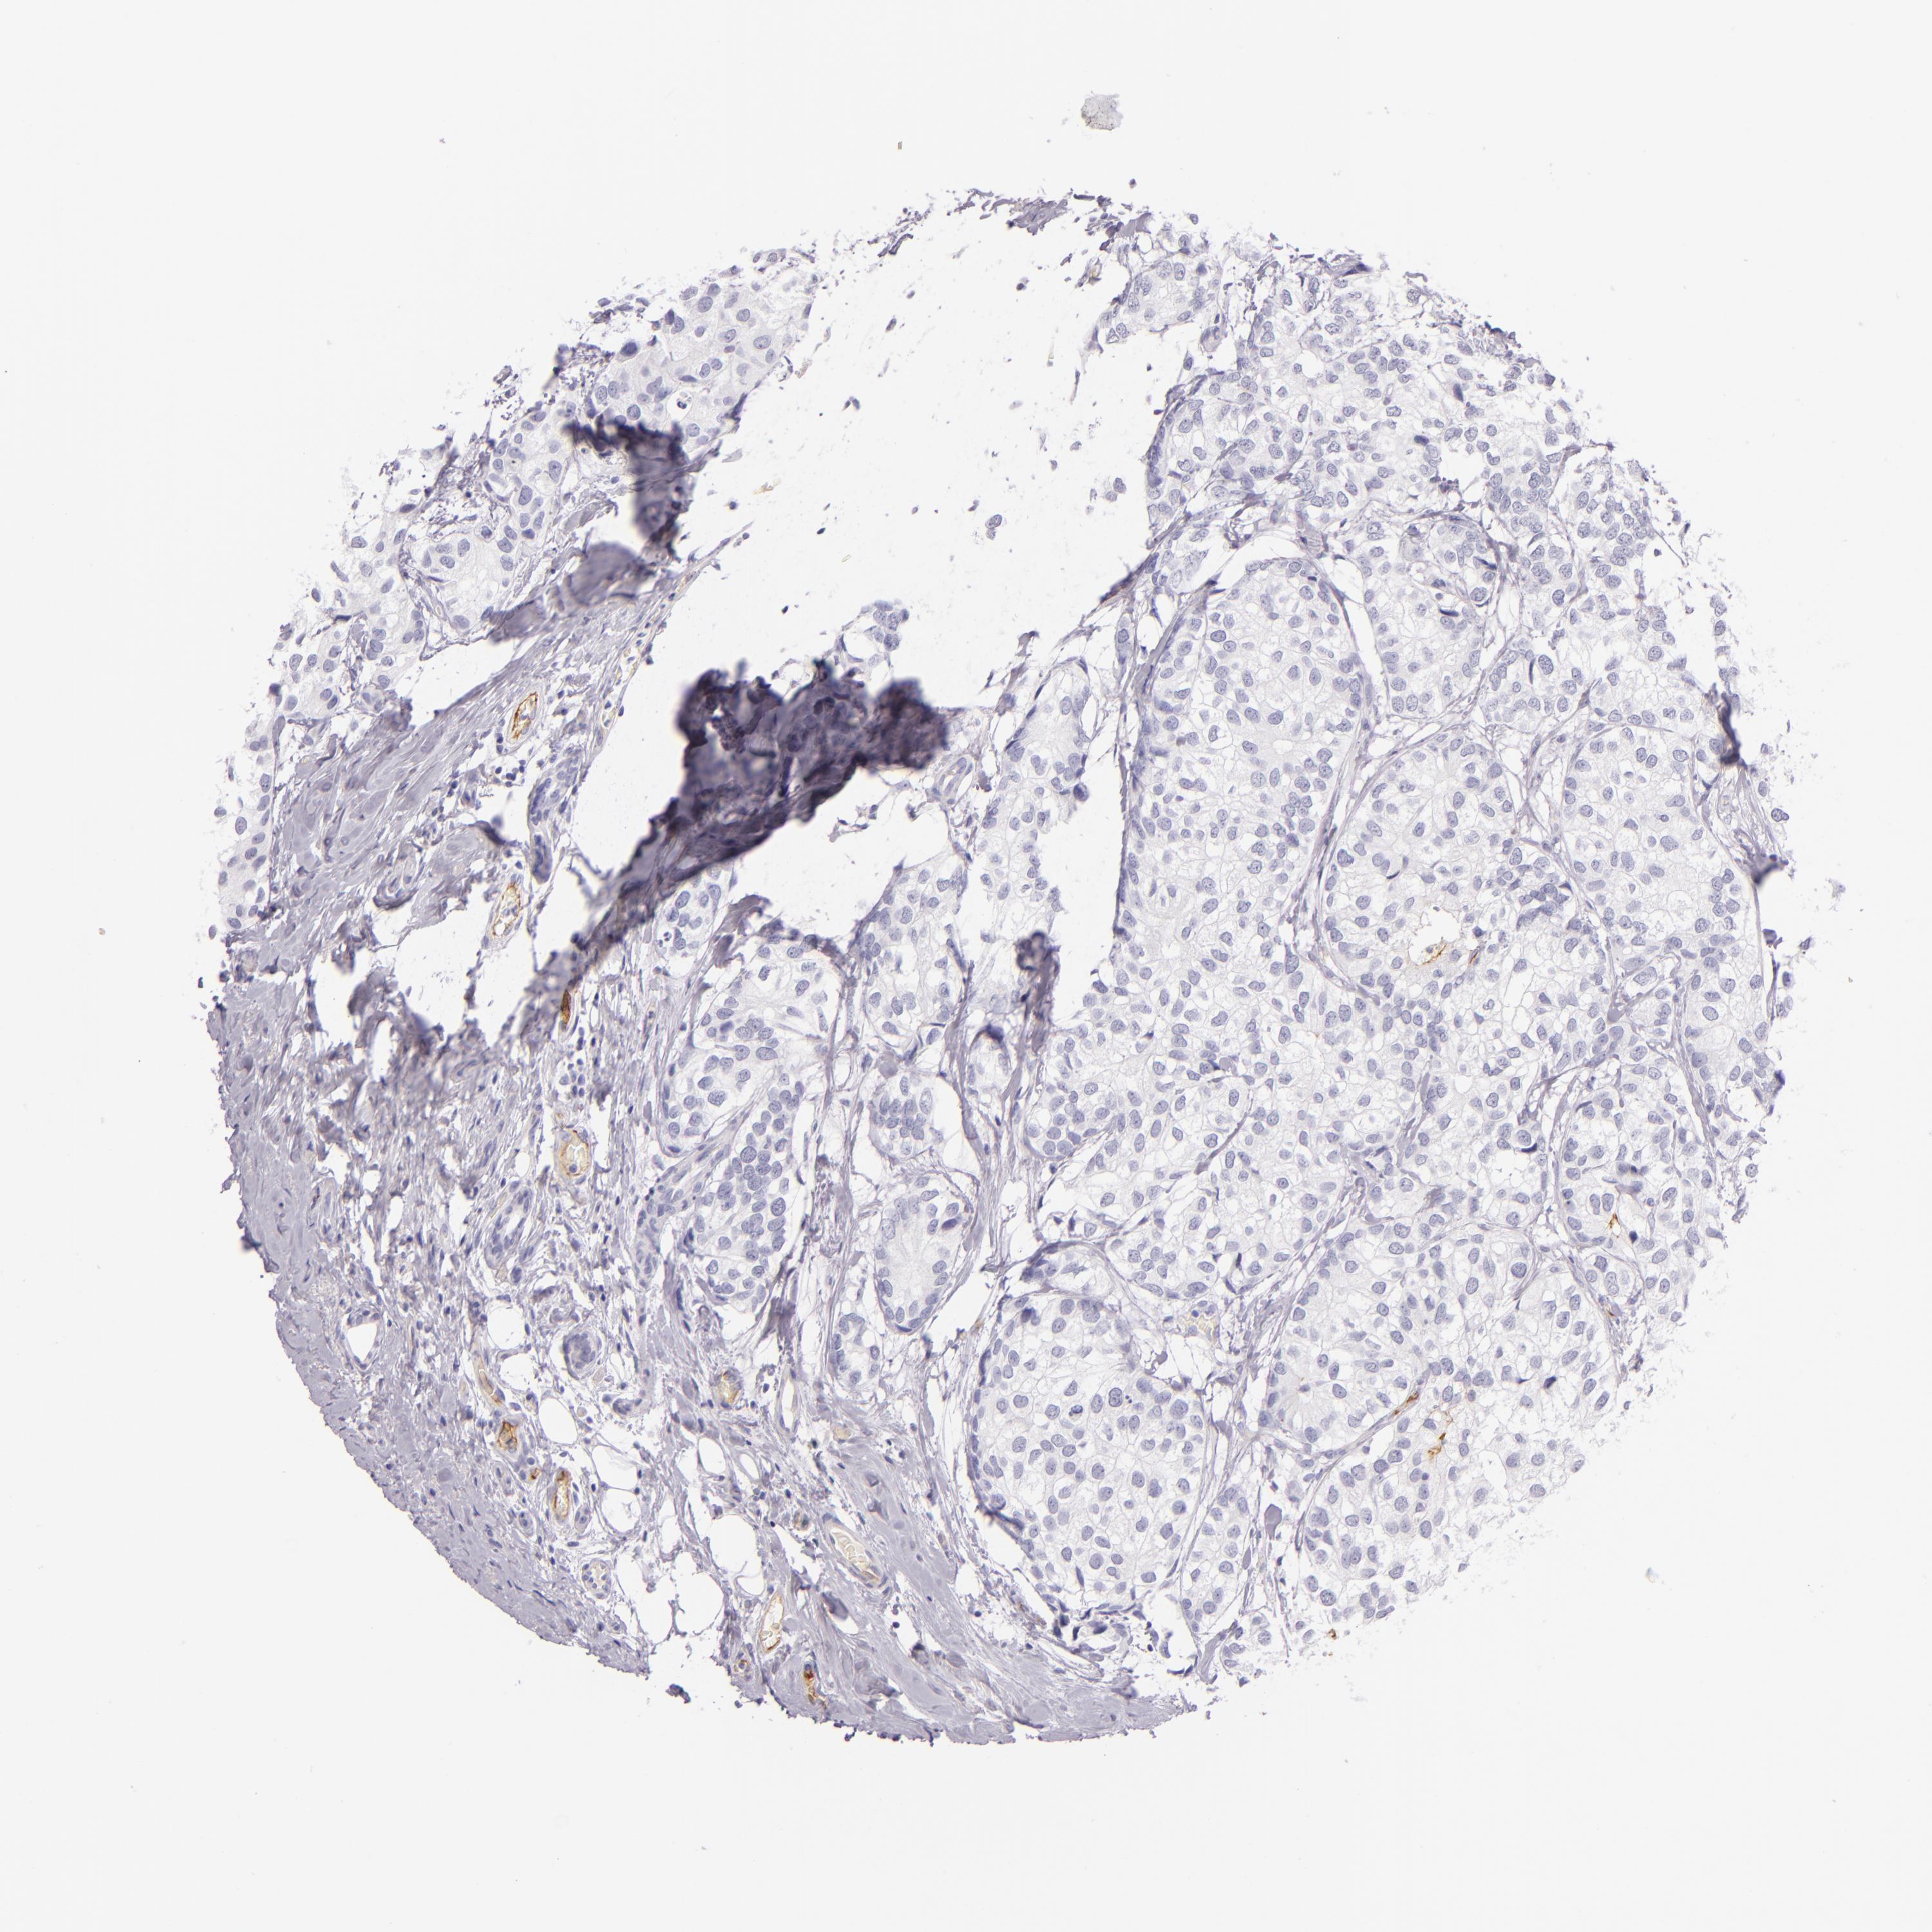

BRCA TCGA BRCA VALIDATION PROTEIN EXPRESSION

ANTIBODIES

AND

VALIDATION